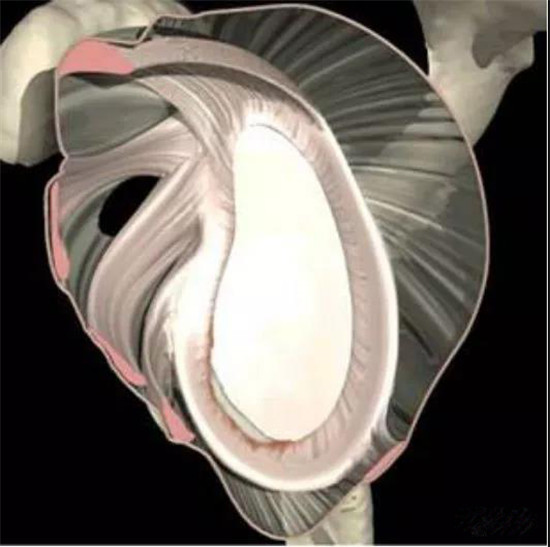

(六)肩袖

肩袖又称旋转袖、肌腱袖是指由冈上肌、冈下肌、小圆肌及肩胛下肌四块肌肉的肌腱所组成的彼此相连的腱板,并且与关节囊紧密相连的一种结构。它的作用在于加固肱骨头与关节盂的连接,对加强肩关节起一定作用。此外它还有使肩关节回旋和外展的作用。

1.冈上肌位于肩胛冈上方的冈上窝,止于肱骨大结节的上端。肩峰下滑囊将其与肩峰、三角肌和喙肩韧带相隔离。

2.冈上肌的下方为冈下肌,走行于冈下窝,止于肱骨大结节的中段。

3.再往下为小圆肌,止于肱骨大结节的下端。这三条肌腱形成肩袖的上后部分,肌腱之间分界不明显。

4.肩袖的前部分为肩胛下肌,走行与肩胛骨的前面,止于肱骨小结节。